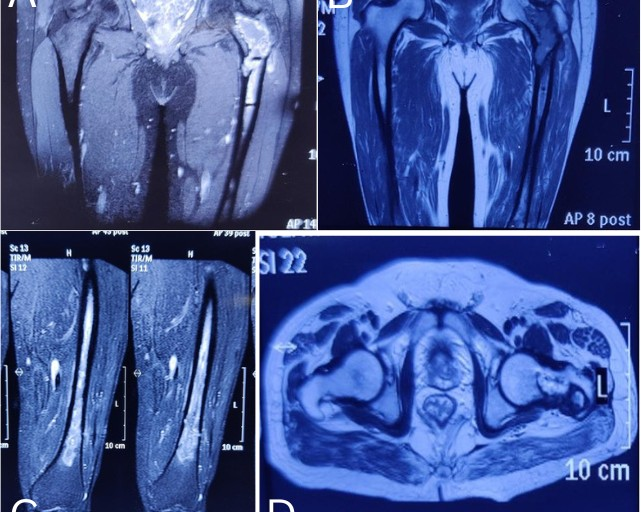

A 52-year-old male presented to our institute with complaints of pain in his left groin and thigh for 3 months. He underwent total hip replacement 4 years ago in another hospital. He had no recent history of trauma, fever, loss of appetite, or any local pus discharge. He was a known case of diabetes mellitus for the past 10 years. His pain was insidious in onset, progressive, and dull-aching in nature. He had a history of trivial trauma followed by an inter-trochanteric femur fracture that was managed with proximal femur nailing 8 years back. Three years later, he developed swelling with a discharged sinus in his left proximal thigh. Initially, it was managed with oral antibiotics. Later, he underwent 3 series of local debridement and finally implant removal. The sequence of past procedures following in chronological order: Proximal femur nailing → osteomyelitis → debridement → THA. The radiology (Fig. 1 and 2) and histopathology were suggestive of chronic osteomyelitis. However, the culture was not positive for any specific organism. Finally, his total hip was replaced after 1 year and 5 months following subsidence of infection.

Figure 1: The magnetic resonance imaging shows the osteomyelitis of the left proximal femur.

Figure 2: The computed tomography scan shows the lytic lesion in the left femur neck and trochanteric region during osteomyelitis.